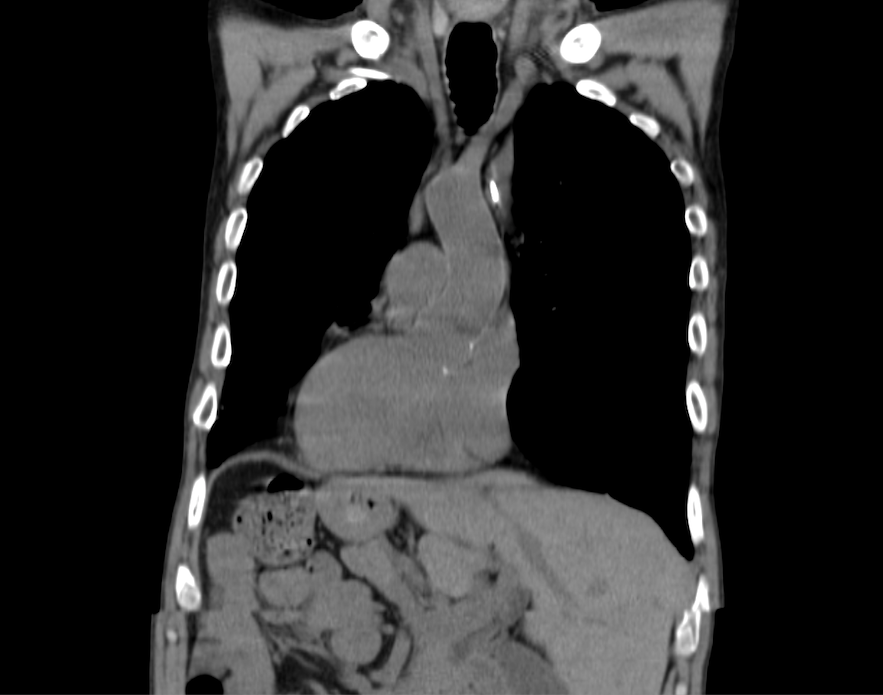

The best explanation for the CXR and EKG findings is dextrocardia. (This is easier to see on the CT scan below.) But there’s more going on than just isolated dextrocardia. In order to understand the unifying diagnosis we need to understand what cilia are and what they do. Image